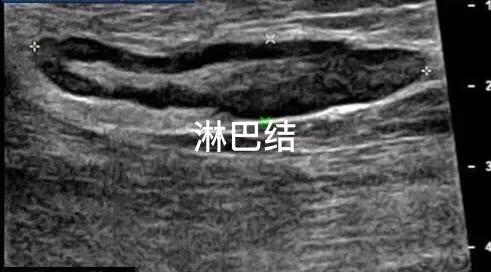

浅表淋巴结应用超声检查方便而且安全

超声观察淋巴结已经应用很长一段时间,超声可以通过观察淋巴结的大小、形态、内部结构变化、是否有钙化、与周围组织的分界等声像改变来分类出严重程度的提示。有时候原发癌症没找到,但是先发现淋巴结的异常肿大,反过来寻找原发癌症的来源。譬如周围脏器的肿瘤确切声像,通过淋巴结穿刺活检病理结果,分辨原发肿瘤来源等。